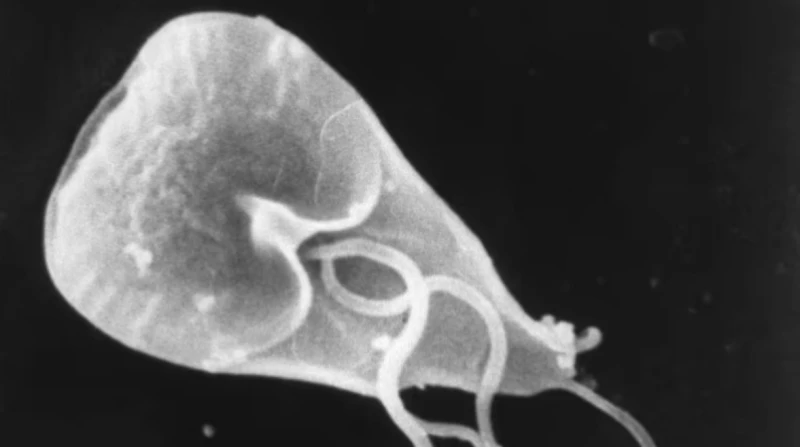

🔸 ما هو داء الجيارديا؟

داء الجيارديات هو الاسم الذي يطلق على مرض في الجهاز الهضمي، يسببه طفيل صغير يسمى الجيارديا لامبليا، وتصيب الإنسان عن طريق الجهاز الهضمي، حيث تنتقل إلى الأمعاء الدقيقة في الجسم مسببة الجرثومة.